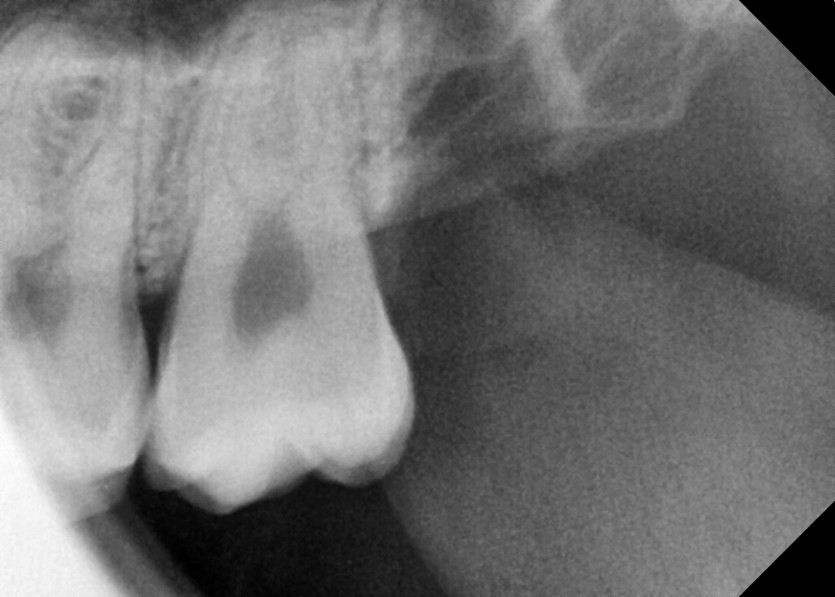

#18,28,38,48 사랑니 발치

구강 외과 전문의가 당일 발치했습니다.